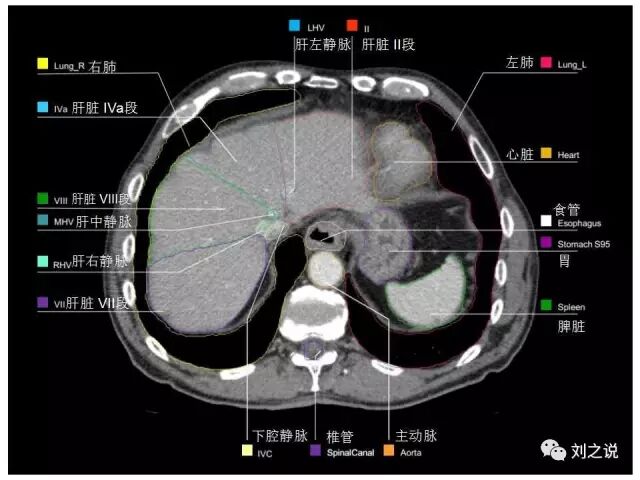

参考RTOG共识和3D-body解剖。

来源:刘之说